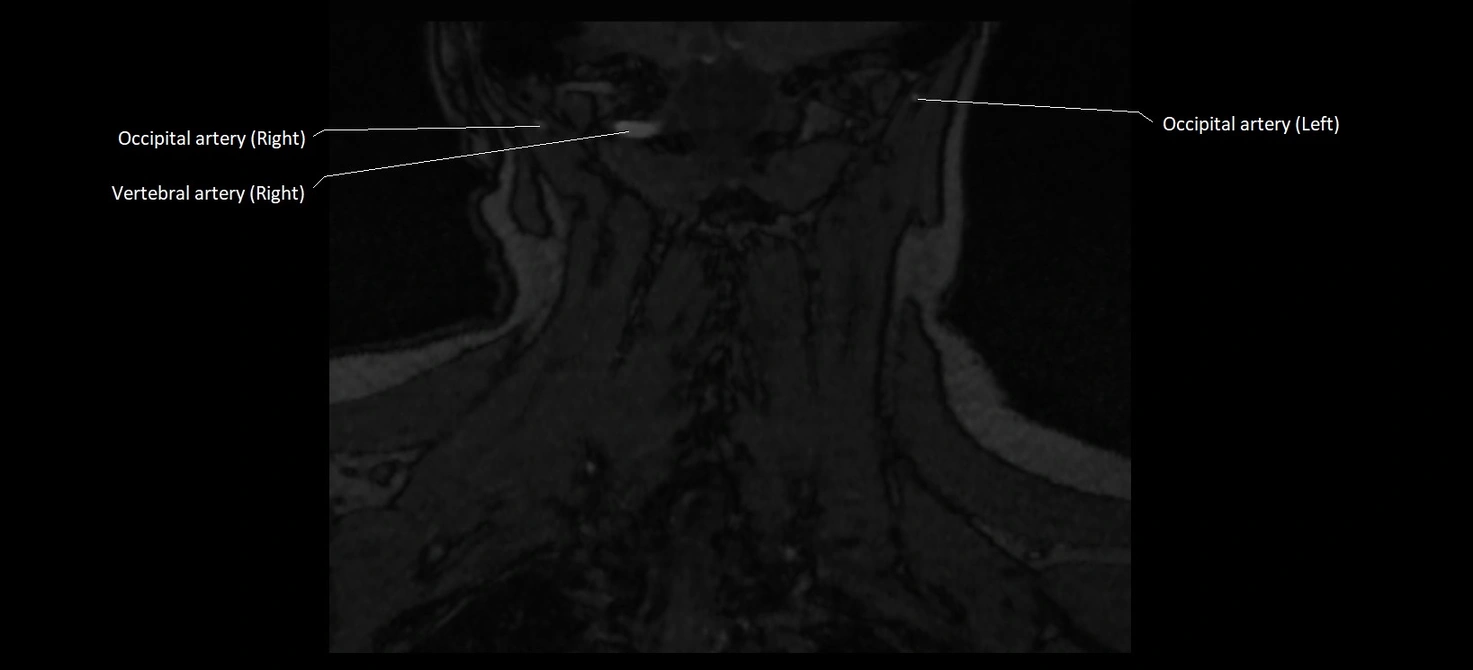

CT image

image